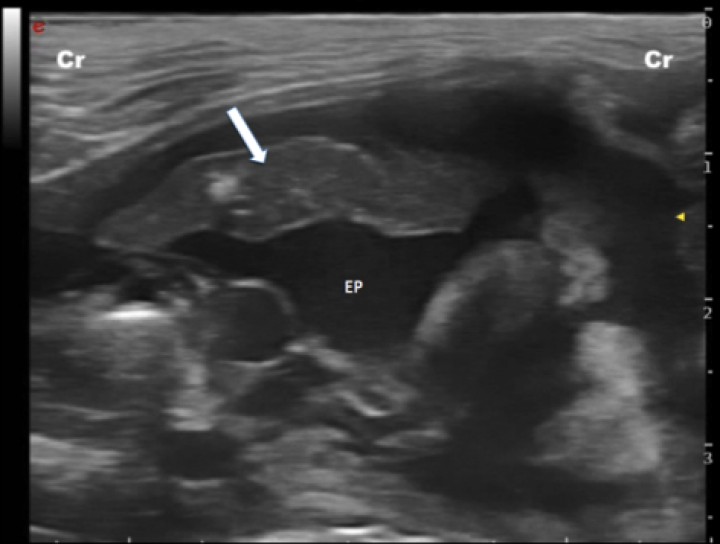

Por último, otra patología fácilmente reconocible en una ecografía torácica de urgencias es la consolidación pulmonar; la cual se define como pulmón con ecogenicidad y ecotextura similar al hígado (pulmón hepatizado).[ L. Cole, M. Pivetta, K. Humm: Diagnostic accuracy of a lung ultrasound protocol (Vet BLUE) for detection of pleural fluid, pneumothorax and lung pathology in dogs and cats. Journal of Small Animal Practice 2021; 62: 178-186. [PubMed] ] Un hallazgo ecográfico es el denominado “signo de escalón”, el cual se define como la discontinuidad de la línea hiperecoica que genera la línea PP (Fig. 7).[ Lisciandro G: Abdominal and thoracic focused assessment with sonography for trauma, triage, and monitoring in small animals. J Vet Emerg Crit Care 2011; 21(2): 104-122. [PubMed] , Lisciandro GR: The abdominal FAST (AFAST) exam. En Lisciandro GR (ed): Focused ultrasound techniques for the small animal practitioner, Oxford, Wiley Blackwell, 2014; 17-43. ] Este también puede deberse a desgarros intercostales, fracturas costales, hematomas y hemotórax en pacientes traumatizados, así como a efusión pleural o masas en pacientes no traumatizados.[ Lisciandro G: Abdominal and thoracic focused assessment with sonography for trauma, triage, and monitoring in small animals. J Vet Emerg Crit Care 2011; 21(2): 104-122. [PubMed] , Lisciandro GR: The abdominal FAST (AFAST) exam. En Lisciandro GR (ed): Focused ultrasound techniques for the small animal practitioner, Oxford, Wiley Blackwell, 2014; 17-43. ] Entre los diagnósticos diferenciales más probables de consolidación pulmonar cabe destacar la presencia de un foco neumónico, hemorragia pulmonar, neoplasia o atelectasia.[ Lisciandro GR: The abdominal FAST (AFAST) exam. En Lisciandro GR (ed): Focused ultrasound techniques for the small animal practitioner, Oxford, Wiley Blackwell, 2014; 17-43. ]

<p>Imagen ecográfica de un paciente con efusión pleural (EP) severa y consolidación pulmonar (flecha blanca) secundaria a la presión ejercida por el líquido sobre el lóbulo pulmonar. Cr: craneal.</p>

Imagen ecográfica de un paciente con efusión pleural (EP) severa y consolidación pulmonar (flecha blanca) secundaria a la presión ejercida por el líquido sobre el lóbulo pulmonar. Cr: craneal.